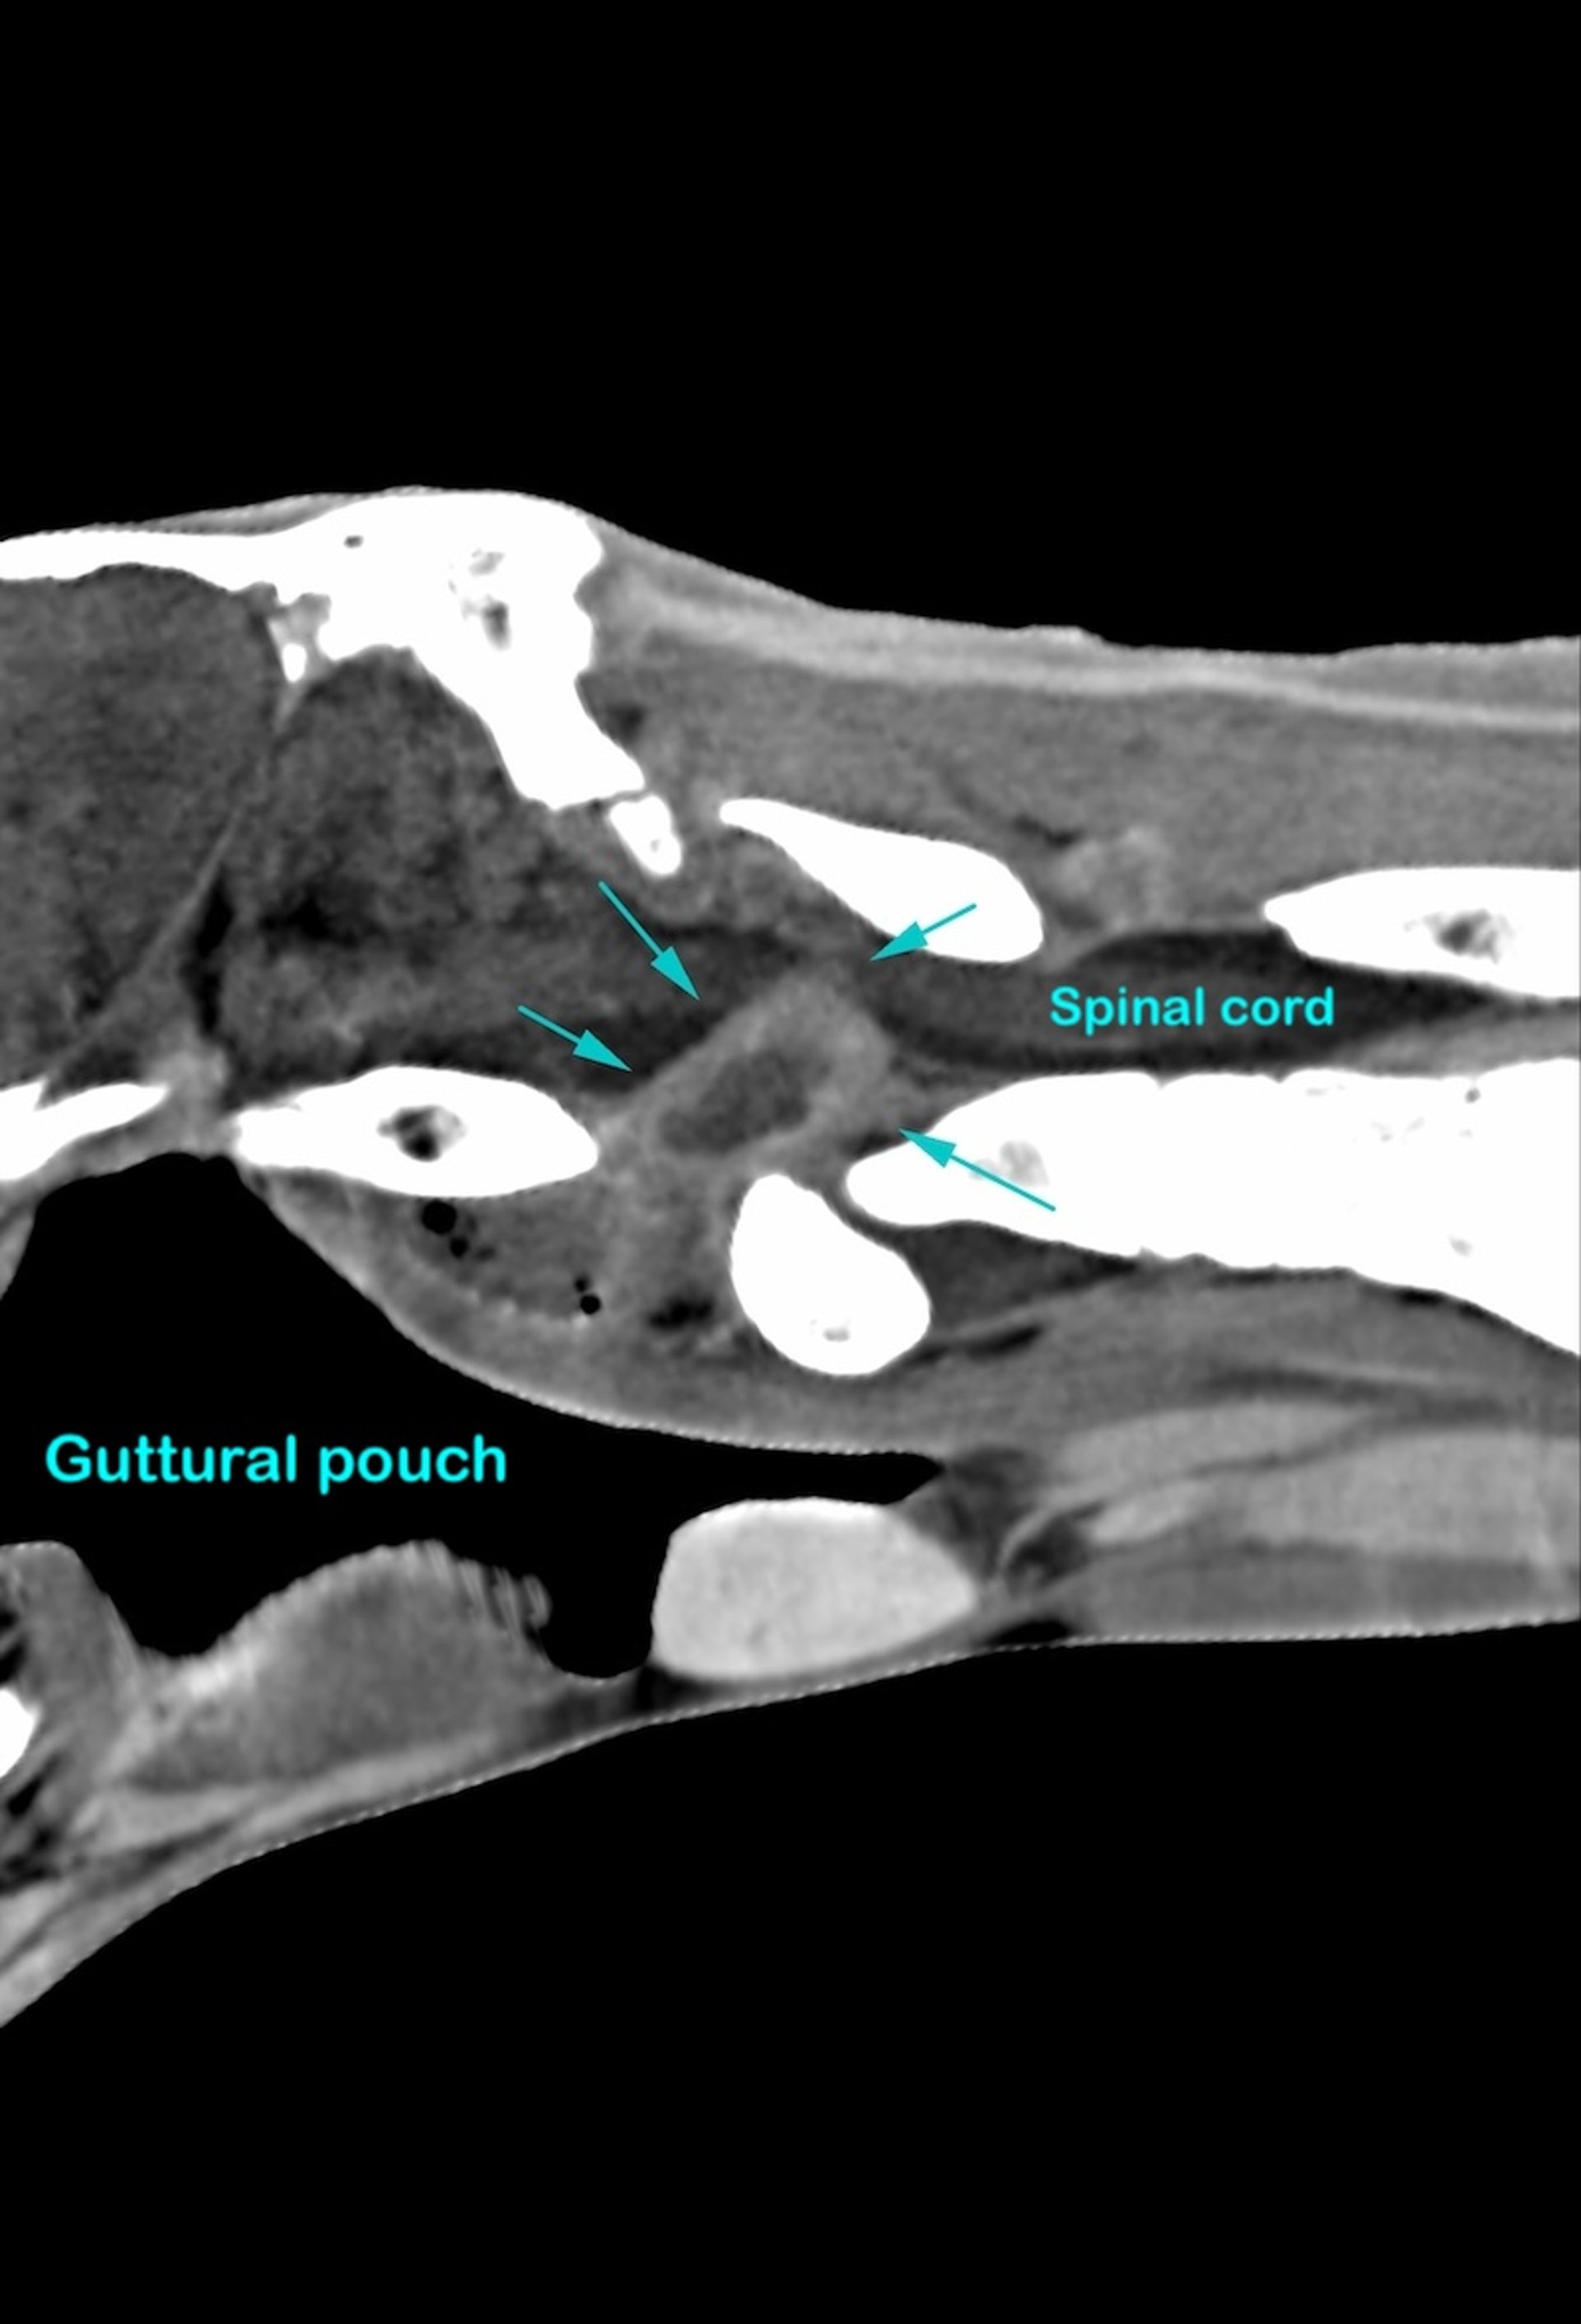

Evaluación por TC reconstruida sagital de la región cervical craneal en un caballo con dolor de cuello. Craneal está a la izquierda. Las flechas indican una masa extradural redondeada de tejido blando con contraste mejorado compatible con empiema/absceso extradural. Esta lesión no sería apreciable en las radiografías y el grado de afectación de la médula espinal ciertamente no sería visible en la radiografía simple.

Cortesía del Dr. Timothy Manzi.